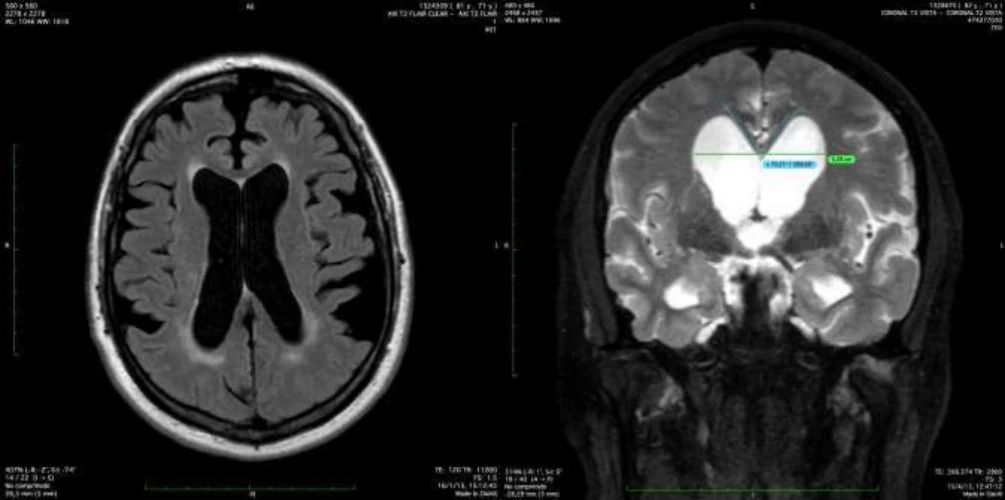

Hallazgos en Resonancia Magnética – Índice de Evans y Ángulo Calloso

La resonancia es realmente una herramienta muy precisa para hacer el diagnóstico:

Edema transependimario: Primero porque se ve el edema transependimario, que se ve como esta zona blanca alrededor de los ventrículos.

Ángulo calloso: Después porque hay unos ángulos que se pueden medir. Este ángulo que es agudo, menor de 90º, es porque el globo ventricular, como esta estructura del cuerpo calloso es muy fija, lo que va a hacer el aumento de presión de los ventrículos es cerrarlo sobre esa estructura.

Índice de Evans: Y después también hay un índice que es la relación entre toda la corteza cerebral de esta longitud y la longitud del ventrículo.

Aparte de eso se puede acabar haciendo estudios muy sofisticados de cómo circula el líquido cefalorraquídeo por el acueducto, de manera que se puede acabar teniendo una clara idea de que estamos ante una hidrocefalia arreabsortiva.